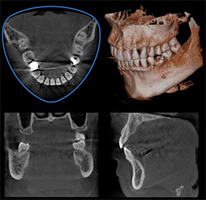

インプラント治療を行う設備

最新の歯科用CTを完備

CTはVeraviewepocs 3Dfを導入しております。他にもCT機器の種類はたくさんあります。

ではなぜ、このCTでなければならないのか?一般に歯科用の CTは機能面も含めて非常に優秀です。

低被爆にも関わらず、非常に高画質な撮影が可能です。その中においても、当院で導入している機種は、CT撮影であることを意識させないレベルでの撮影時間の短さや被爆量の少なさが売りです。それでいて画像が鮮明であることなど、撮影される側の患者様にとって「どうしても撮らなければいけないのなら、これがいい」と思っていただける機種を選択しました。

他にも撮影されている際に必要以上に固定する必要性がなく、圧迫感のない非常に楽な姿勢で撮影ができる点もお勧めのポイントになります。

一般に治療を行う上で情報が多くて困るということはございません。

例えば、がんの手術を行うには血液検査から造影CTやMRIなど多岐に渡った検査結果を持ちよって治療にあたります。がんではなく良性の腫瘍であっても検査はたくさん必要になります。

インプラント治療は腫瘍を切除するようなものではありませんが、二次元の画像では把握できない情報を多く与えてくれます。単に骨の厚みがあるかないかを診るだけのツールではありません。

したがって、いかなる症例においてもインプラント治療を行う上で、CT撮影の情報というものは非常に重要である

ことは言うまでもありません。

「必要な場合にはCTを撮影します」という歯科医師がおります。

CT画像を読むという行為は、日頃から習慣として訓練しているからこそ読影できるようになるものです。

これを普段から怠っているのですから、彼らにとって必要になった場合の画像の情報は恐らく10分の1も活用できていないことは明らかです。

恐らく骨の幅や血管の走行(骨の中に太い血管が通っているところがあります)だけを見ているだけでしょう。

患者様に非常に無駄な被爆をさせていると言えます。